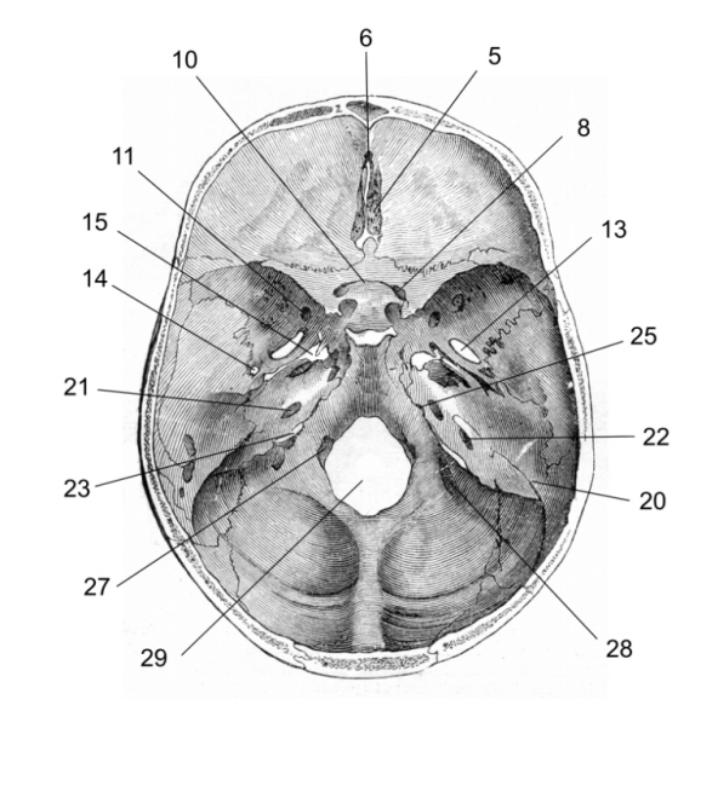

Анатомические детали: Фотографии топографии черепа с нижнего вида

Раздел: Альбом идей